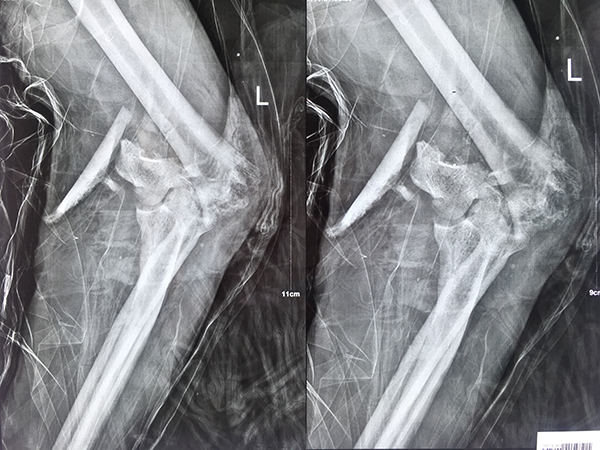

圖為 患者術(shù)前左肘部位圖

簡單來說就是,取骨重建!這是一種較為困難且復雜的骨折修復手術(shù),通過手術(shù)將患者體內(nèi)特定部位的骨質(zhì)取出、進行打磨修整,使其盡可能的恢復正常生理解剖結(jié)構(gòu)后,再補充到受傷部位進行固定,達到修復重建的效果。

髂骨是最常用的自體骨移植物,由于是自體骨移植,不用擔心組織相容性及移植后的排異反應(yīng),而且髂骨的移植并不會對患者的正常工作和生活造成太大影響,所以取骨重建能達到十分理想的修復效果。